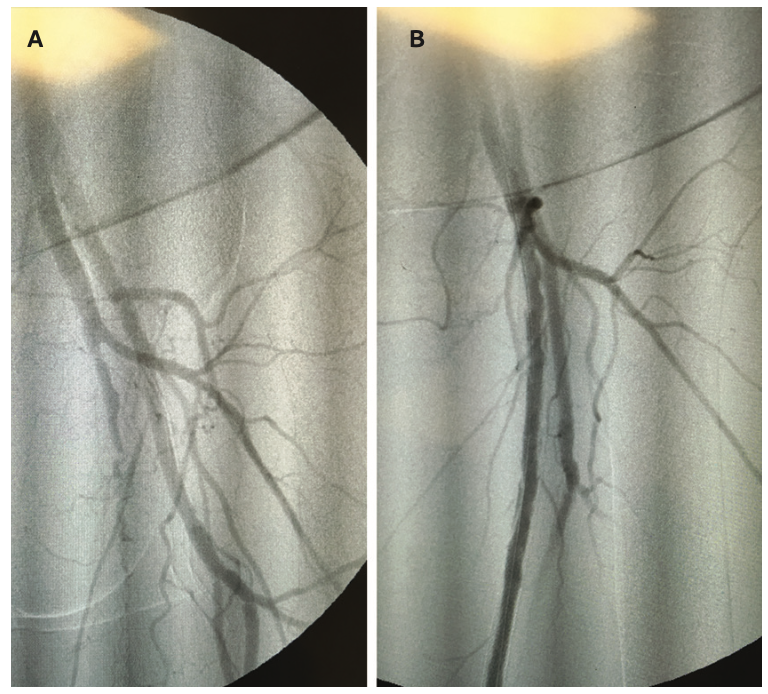

Once a patient presents with CLI, options of care are limited to amputation, peripheral vascular intervention (PVI), or a combination of both. Bypass may also be a consideration, dependent on the extent of blockage in the distal arteries, but often, once a patient presents with CLI, the disease state has progressed beyond the point of bypass being an option. Although there are risk factors with each treatment option, amputation carries a higher level of risk given the possibility of complications from an invasive surgical procedure, deep sedation, and the trauma of losing a limb. For below-the-knee amputations (BKA), a 2023 analysis by Beeson et al reported mortality rates of 4.18% at 30 days, 7.50% at 90 days, 10.88% at 1 year, and 16.67% at 5 years.3 Above-the-knee amputation (AKA) carries a higher risk of mortality, with rates at 9.27% at 30 days, 14.73% at 90 days, 19.40% at 1 year, and 24.49% at 5 years (Figure 1).3 Lower limb amputation has a significant impact on quality of life, as it not only affects the patient’s socioeconomic status and impairs mobility, but also has a systemic effect on the entire body. Patients can experience phantom limb pain, muscle contractures, fatigue, psychological issues with confidence and self-esteem, and have an increased fall risk due to changes in their center of gravity.